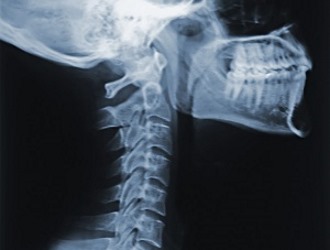

С греческого языка термин «лордоз» переводится как «согнутый» или «сутулый». В медицинской практике это слово используется для обозначения естественных изгибов позвоночника в шейном и поясничном отделах, которые имеют выпуклость, направленную вперед. Эти изгибы играют важную роль в снижении нагрузки на позвоночник во время движения.

Гиполордоз, или выпрямление физиологических изгибов позвоночника, представляет собой патологическое состояние, при котором наблюдается выпрямление естественных изгибов в области шеи или поясницы.

При гиполордозе изгиб, направленный назад, становится менее выраженным.

В заключение следует подчеркнуть, что специалисты могут переоценивать степень сглаженности лордоза при анализе рентгеновских снимков. Часто в заключениях рентгенологов можно встретить фразу «поясничный лордоз сглажен».

В большинстве случаев это состояние является компенсаторной реакцией на неправильную осанку и не считается патологическим. В таких ситуациях уплощение лордоза происходит для оптимального перераспределения нагрузки. Этот симптом обычно исчезает самостоятельно после коррекции осанки. В других случаях гиполордоз требует медицинского вмешательства.